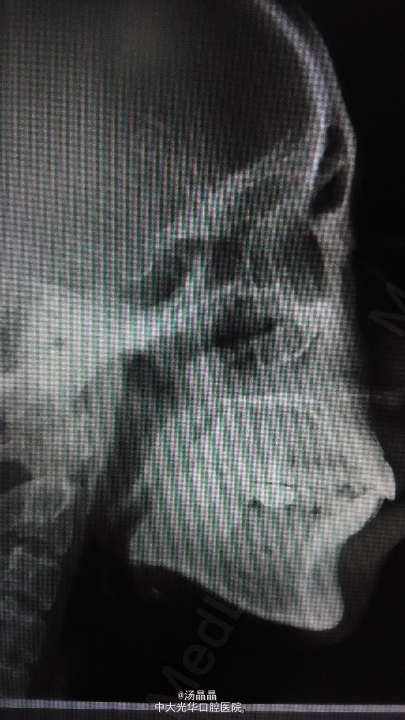

患者,女,30岁,发现双颌前突20余年

面上中下三分之一比例协调,侧面观可见上下唇前突,双侧颞下颌关节运动无明显异常,开口度4厘米,口内检查可见上下颌全口正畸弓丝及托槽,18,28,48阻生,46缺失

诊断为双颌前突,全麻下行双侧上下颌前牙根尖下截骨后退术,双侧上下颌骨部分切除术,上下颌骨内坚固内固定术,14,24,34,44复杂牙拔除术,植入Martin钛板4块,钛钉16颗固定